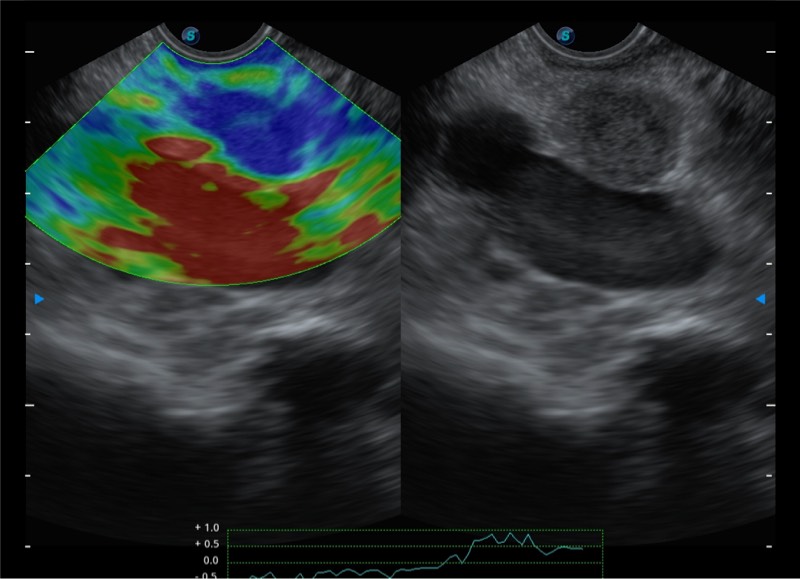

基于二十年的超声技术积累,百老汇电子游戏官网提供了最新一代的独立超声主机,在提供高质量图像的同时满足多学科使用。具备常见多普勒技术并提供弹性成像、声学造影等高端影像技术。新一代传感器具有更强的抗干扰能力并减少图像伪影。

4-12MHZ宽频输出